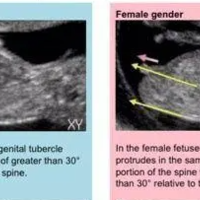

nub实际上就是胎儿的生殖节,一般在胎儿11-13周的时候,两腿之间的生殖器部位开始发育,这时候的男胎儿和女胎儿的生殖节从外表上来看其实都是一样的。只不过不同的是:生殖节的角度不一样,男胎儿的生殖节一般是向上翘,和脊柱线呈30度或者以上的角度;而女胎儿的生殖节则和脊柱线呈小于30度的角度,甚至平行或者负角度。下面就给大家分享胎儿nub节点位置的标准图。网络上流传的可以通过NT结果看男女,其实就是通

三个亮点在胎儿腿根部靠近臀部的地方,首先,大家要找到胎儿的双腿,在NT图中,胎儿的双腿与nub点有明显的区别,胎儿的腿会比nub点长一些。接着,在胎儿双腿根部靠近屁股的位置寻找一个像尾巴一样向外凸起的地方,这个凸起的地方就是nub点,通过nub点的角度和起伏,大家就可以看出孩子是否是男宝宝。一般大家可以在怀孕11-13周进行NT检查,因为此时胎儿生长发育较快,男女特征较为明显,有利于观察,nub点